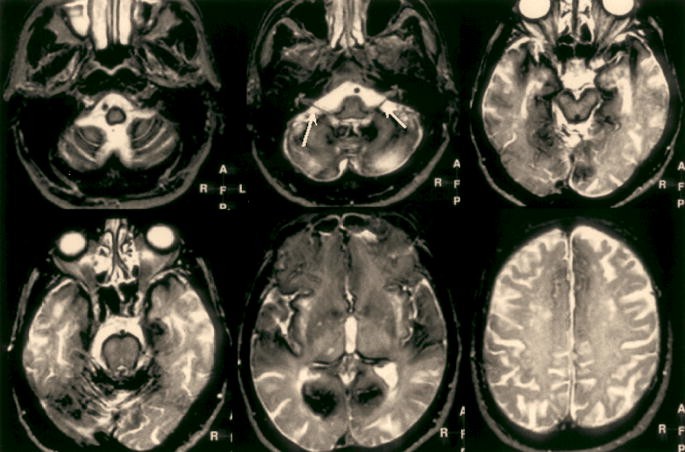

Um die Diagnose zu bestätigen, kann der Arzt verschiedene bildgebende Verfahren anwenden. Eine der häufigsten Methoden ist die Röntgenaufnahme der Lunge. Diese kann helfen, Anzeichen von Eisenansammlungen in der Lunge zu erkennen. In einigen Fällen kann auch eine Computertomographie (CT) oder Magnetresonanztomographie (MRT) erforderlich sein, um detailliertere Bilder der Lunge und anderer betroffener Organe zu erhalten.